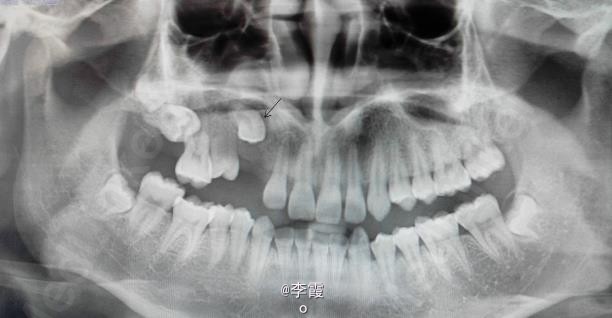

患者、陆xx、男、17岁。主诉:右侧上后牙未萌出,要求治疗。平素体质一般,无药物、食物过敏史,无高血压、心脏病等系统性疾病。

口腔专科检查:13、14和17未萌出。15 牙齿90°扭转萌出,左侧上颌牙齿均正常萌出。x线 全景片:13牙冠周围有约红枣大小牙囊影。14高位阻生、17水平阻生。

诊断:(1)13含牙囊肿(2)14高位垂直阻生。(3)17高位水平阻生。处理:(1)建议手术拔除15及去除13牙冠周围牙囊,保留13。(2)半年后做13和15正畸牵引。17暂时不做处理。